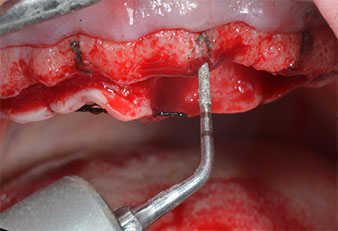

Abb. 2: Nach dem Kieferkammschnitt und der Präparation der Mukoperiostlappen werden die Implantatpositionen auf den Knochen übertragen.

Ein flammenförmiges, diamantiertes piezochirurgisches Instrument (Piezomed I1) wurde verwendet, um die Implantatpositionen zu markieren und die Pilotpräparationen durchzuführen (Abb. 3). Dabei wurde darauf geachtet, eine Auf- und Abbewegung mit reduzierter Leistung, voller Spülung und niedrigem Druck (unter 300 g) anzuwenden. Als Nächstes wurde ein Pilotinstrument (Piezomed I2A/I2P) zur initialen Erweiterung der Implantatlager auf einen Durchmesser von 2 mm verwendet (Abb. 4), gefolgt von einem 3-mm-Instrument (Abb. 5).

Abb. 3: Die Präparation mit dem Ultraschallmarkerinstrument Piezomed I1 erfolgt mit einer Auf- und Abbewegung, parallel zur Längsachse des Arbeitsteils.